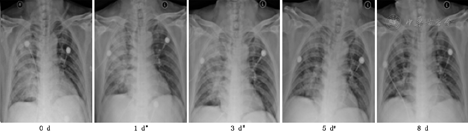

由疾控中心专业人员采样留取两份呼吸道标本(鼻咽分泌物及深部痰)作病毒核酸检测,雾化治疗后1~4 d,4例患者第1次病毒核酸检测转阴,分别间隔24 h以上再次阴性后解除隔离,详见表2。治疗后患者咳嗽、咳痰、胸闷等呼吸道症状及发热等症状逐渐好转,详见表3。呼吸频率、血常规及血气分析均恢复正常,详见表4。复查胸部影像X线检查,肺部原发病灶均逐渐吸收好转,均无新发病灶,详见图1,图2,图3,图4。

注:*表示第一次咽试子及深部痰病毒核酸检测转阴,#表示第二次咽试子及深部痰病毒核酸检测转阴(以下相同)